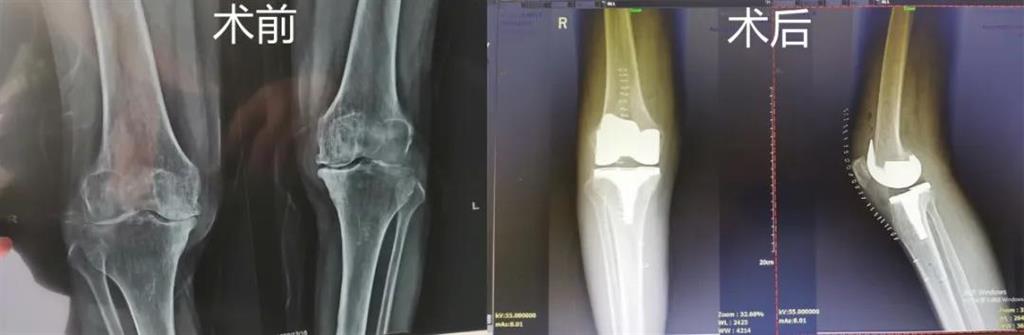

突破!和平國(guó)際醫(yī)院成功完成一例計(jì)算機(jī)導(dǎo)航膝關(guān)節(jié)置換術(shù)

最近,和平國(guó)際醫(yī)院骨科中心開(kāi)展了一項(xiàng)新業(yè)務(wù)——計(jì)算機(jī)導(dǎo)航膝關(guān)節(jié)置換術(shù),而年邁78歲的李奶奶則幸運(yùn)地成為該手術(shù)的首個(gè)受益者。這也是溫州地區(qū)率先將骨科傳統(tǒng)手術(shù)與計(jì)算機(jī)導(dǎo)航系統(tǒng)相結(jié)合應(yīng)用的成功案例,也是和平國(guó)際醫(yī)院骨科中心在膝關(guān)節(jié)置換術(shù)方面所取得的一次重大突破!

李奶奶已經(jīng)被兩側(cè)膝關(guān)節(jié)疼痛困擾了5年左右時(shí)間,尤其是右側(cè)膝關(guān)節(jié),近一年來(lái)癥狀明顯加重,無(wú)法正常生活。經(jīng)過(guò)多方打聽(tīng),一家人來(lái)到和平國(guó)際醫(yī)院。

和平國(guó)際醫(yī)院副院長(zhǎng)、骨科中心主任劉丹在診斷后發(fā)現(xiàn),老人雙側(cè)膝關(guān)節(jié)患有骨性關(guān)節(jié)炎,右側(cè)膝關(guān)節(jié)較為嚴(yán)重,而且關(guān)節(jié)磨損嚴(yán)重,關(guān)節(jié)間隙基本消失。

經(jīng)過(guò)進(jìn)一步檢查后,劉丹帶領(lǐng)團(tuán)隊(duì)在計(jì)算機(jī)導(dǎo)航系統(tǒng)的輔助下,為老人實(shí)施了右側(cè)全膝關(guān)節(jié)置換手術(shù)。術(shù)中出血明顯減少,術(shù)后疼痛腫脹等反應(yīng)輕微,畸形矯正力線恢復(fù)理想,而且功能恢復(fù)快速,術(shù)后四天就可以下地行走。

據(jù)劉丹主任介紹,計(jì)算機(jī)導(dǎo)航膝關(guān)節(jié)置換術(shù)可以避免打開(kāi)股骨髓腔,從而明顯減小手術(shù)創(chuàng)傷減少術(shù)中出血,能夠更精準(zhǔn)地從三維角度調(diào)整手術(shù)截骨方向,恢復(fù)肢體對(duì)線,并能進(jìn)行精確的軟組織平衡,從而使患者獲得良好的術(shù)后功能恢復(fù)。

計(jì)算機(jī)導(dǎo)航膝關(guān)節(jié)置換術(shù)過(guò)程部分畫面